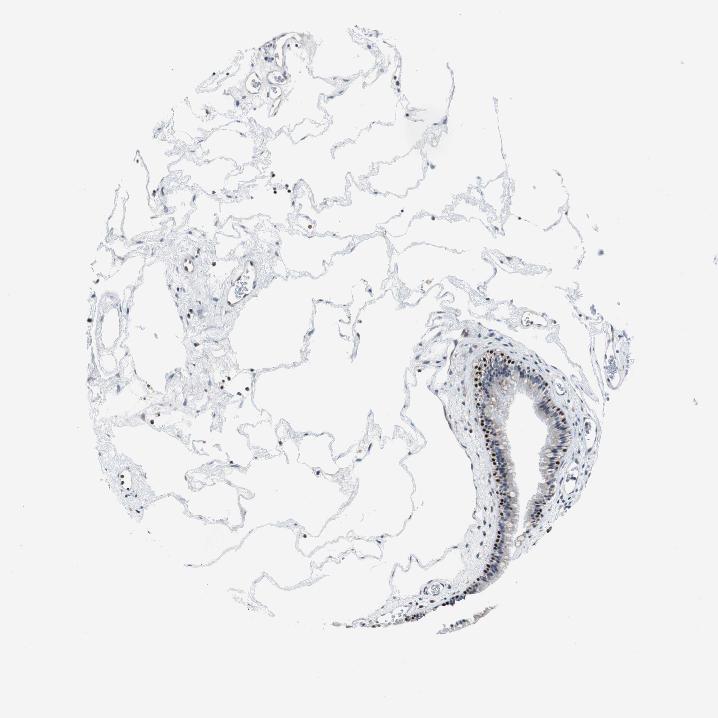

TISSUE PRIMARY DATA NASOPHARYNX Show tissue menu

NASOPHARYNX - Antibody stainingi

Antibody staining in the annotated cell types in the current human tissue is reported as not detected, low, medium, or high, based on conventional immunohistochemistry profiling in selected tissues. This score is based on the combination of the staining intensity and fraction of stained cells.

Each image is clickable and will lead to virtual microscopy that enables deeper exploration of all samples and also displays staining intensity scores, fraction scores and subcellular localization as well as patient and tissue information for each sample.

Antibody HPA006288Antibody HPA007010Antibody CAB000083

Respiratory epithelial cells MediumHighHigh